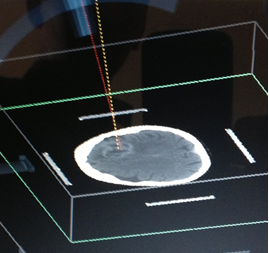

1) MARCO ESTEREOTAXIA: Marcación estereotáctica para lesiones profundas , craneotomias guiada por estereotaxia y/o asistidas por Neuronavegación. (Incluirá el equipo)

VI. CIRUGIA FUNCIONAL , ESTEREOTAXIA Y EPILEPSIA

Se prestará la asistencia para la alternativa terapéutica en casos de enfermedades refractarias a tto médico, cirugía en casos de movimientos